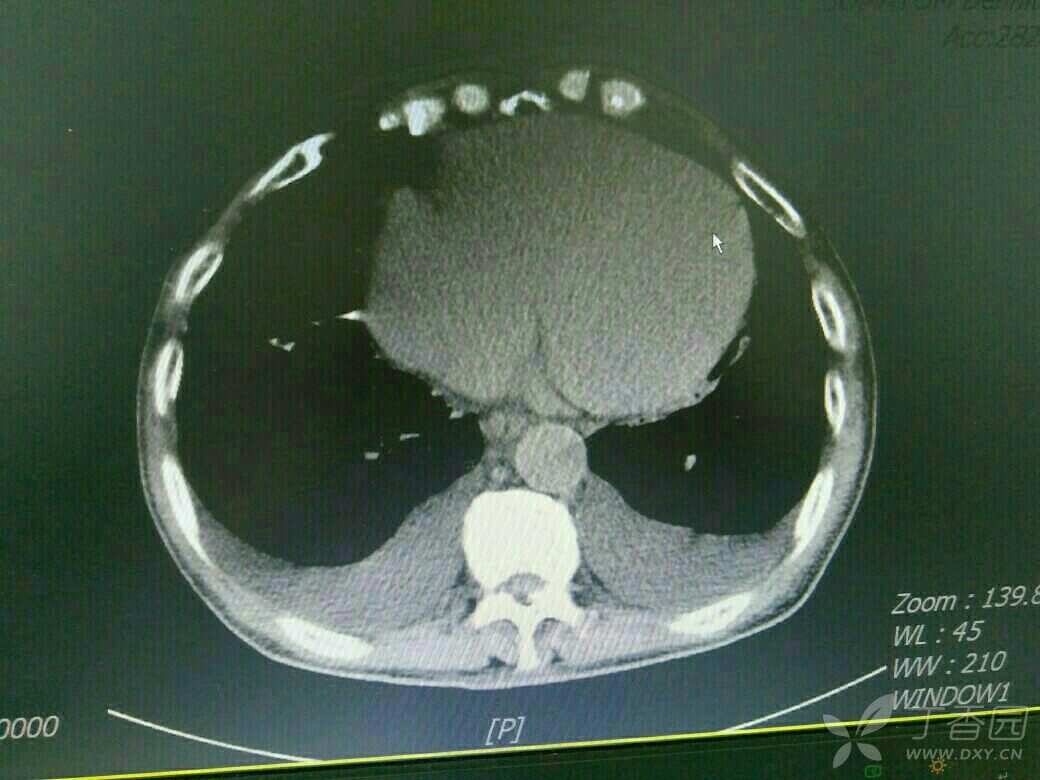

患者71岁老年男性,既往copd,多次住院治疗,平时状态好的时候气促也明显,这次是受凉在当地输液10多天,病情加重入院,来的时候诉乏力气促,上腹胀痛,不能进食,双下肢中度水肿,颈静脉怒张,肝功提示转氨酶400多,bnp6000多,心电图是快速房颤,心脏彩超示EF26%,CT示双侧胸腔积液,肝周积液,门静脉增宽,直径1.8cm,与强心利尿后,来的时候血气还可以,现在血气是呼酸合并代碱